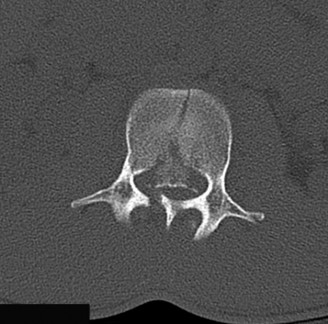

CASE 1 A 63-year-old male sustained a hyperextension injury to his neck while diving into a pool. Upon presentation, he reports decreased sensation in his hands and decreased strength in his arms and wrists, but no lower extremity complaints. On motor examination, he has 5/5 strength in his deltoids and elbow flexors and 4/5 strength in the elbow extensors, wrist extensors, and finger flexors. Lower extremity motor examination is normal. Sensation is decreased to light touch in both hands. Otherwise his sensation is preserved. Images of his cervical spine are shown in Figures 1–1 to 1–3.

Figure 1–3

The correct answer is (B). The clinical scenario describes a patient with central cord syndrome (CCS). CCS continues to be the most common incomplete spinal cord injury accounting for 15.7% to 25% of all spinal cord injuries. The characteristic presentation is an extension moment injury in a previously spondylotic and stenotic spine. Figures 1–1 to 1–3 demonstrate a spondylotic spine with central narrowing and CSF effacement that is worst at the C3–4 level. Bleeding, edema, and/or Wallerian degeneration lead to damage of the lateral corticospinal tract which is the main descending motor tract in the spinal cord. The more central anatomic position of the homunculus to the upper extremities places them at greater risk than those to the lower extremities. As such, injury to the lateral corticospinal tract is characterized by upper more than lower extremity involvement and motor deficits being more pronounced than sensory deficits.